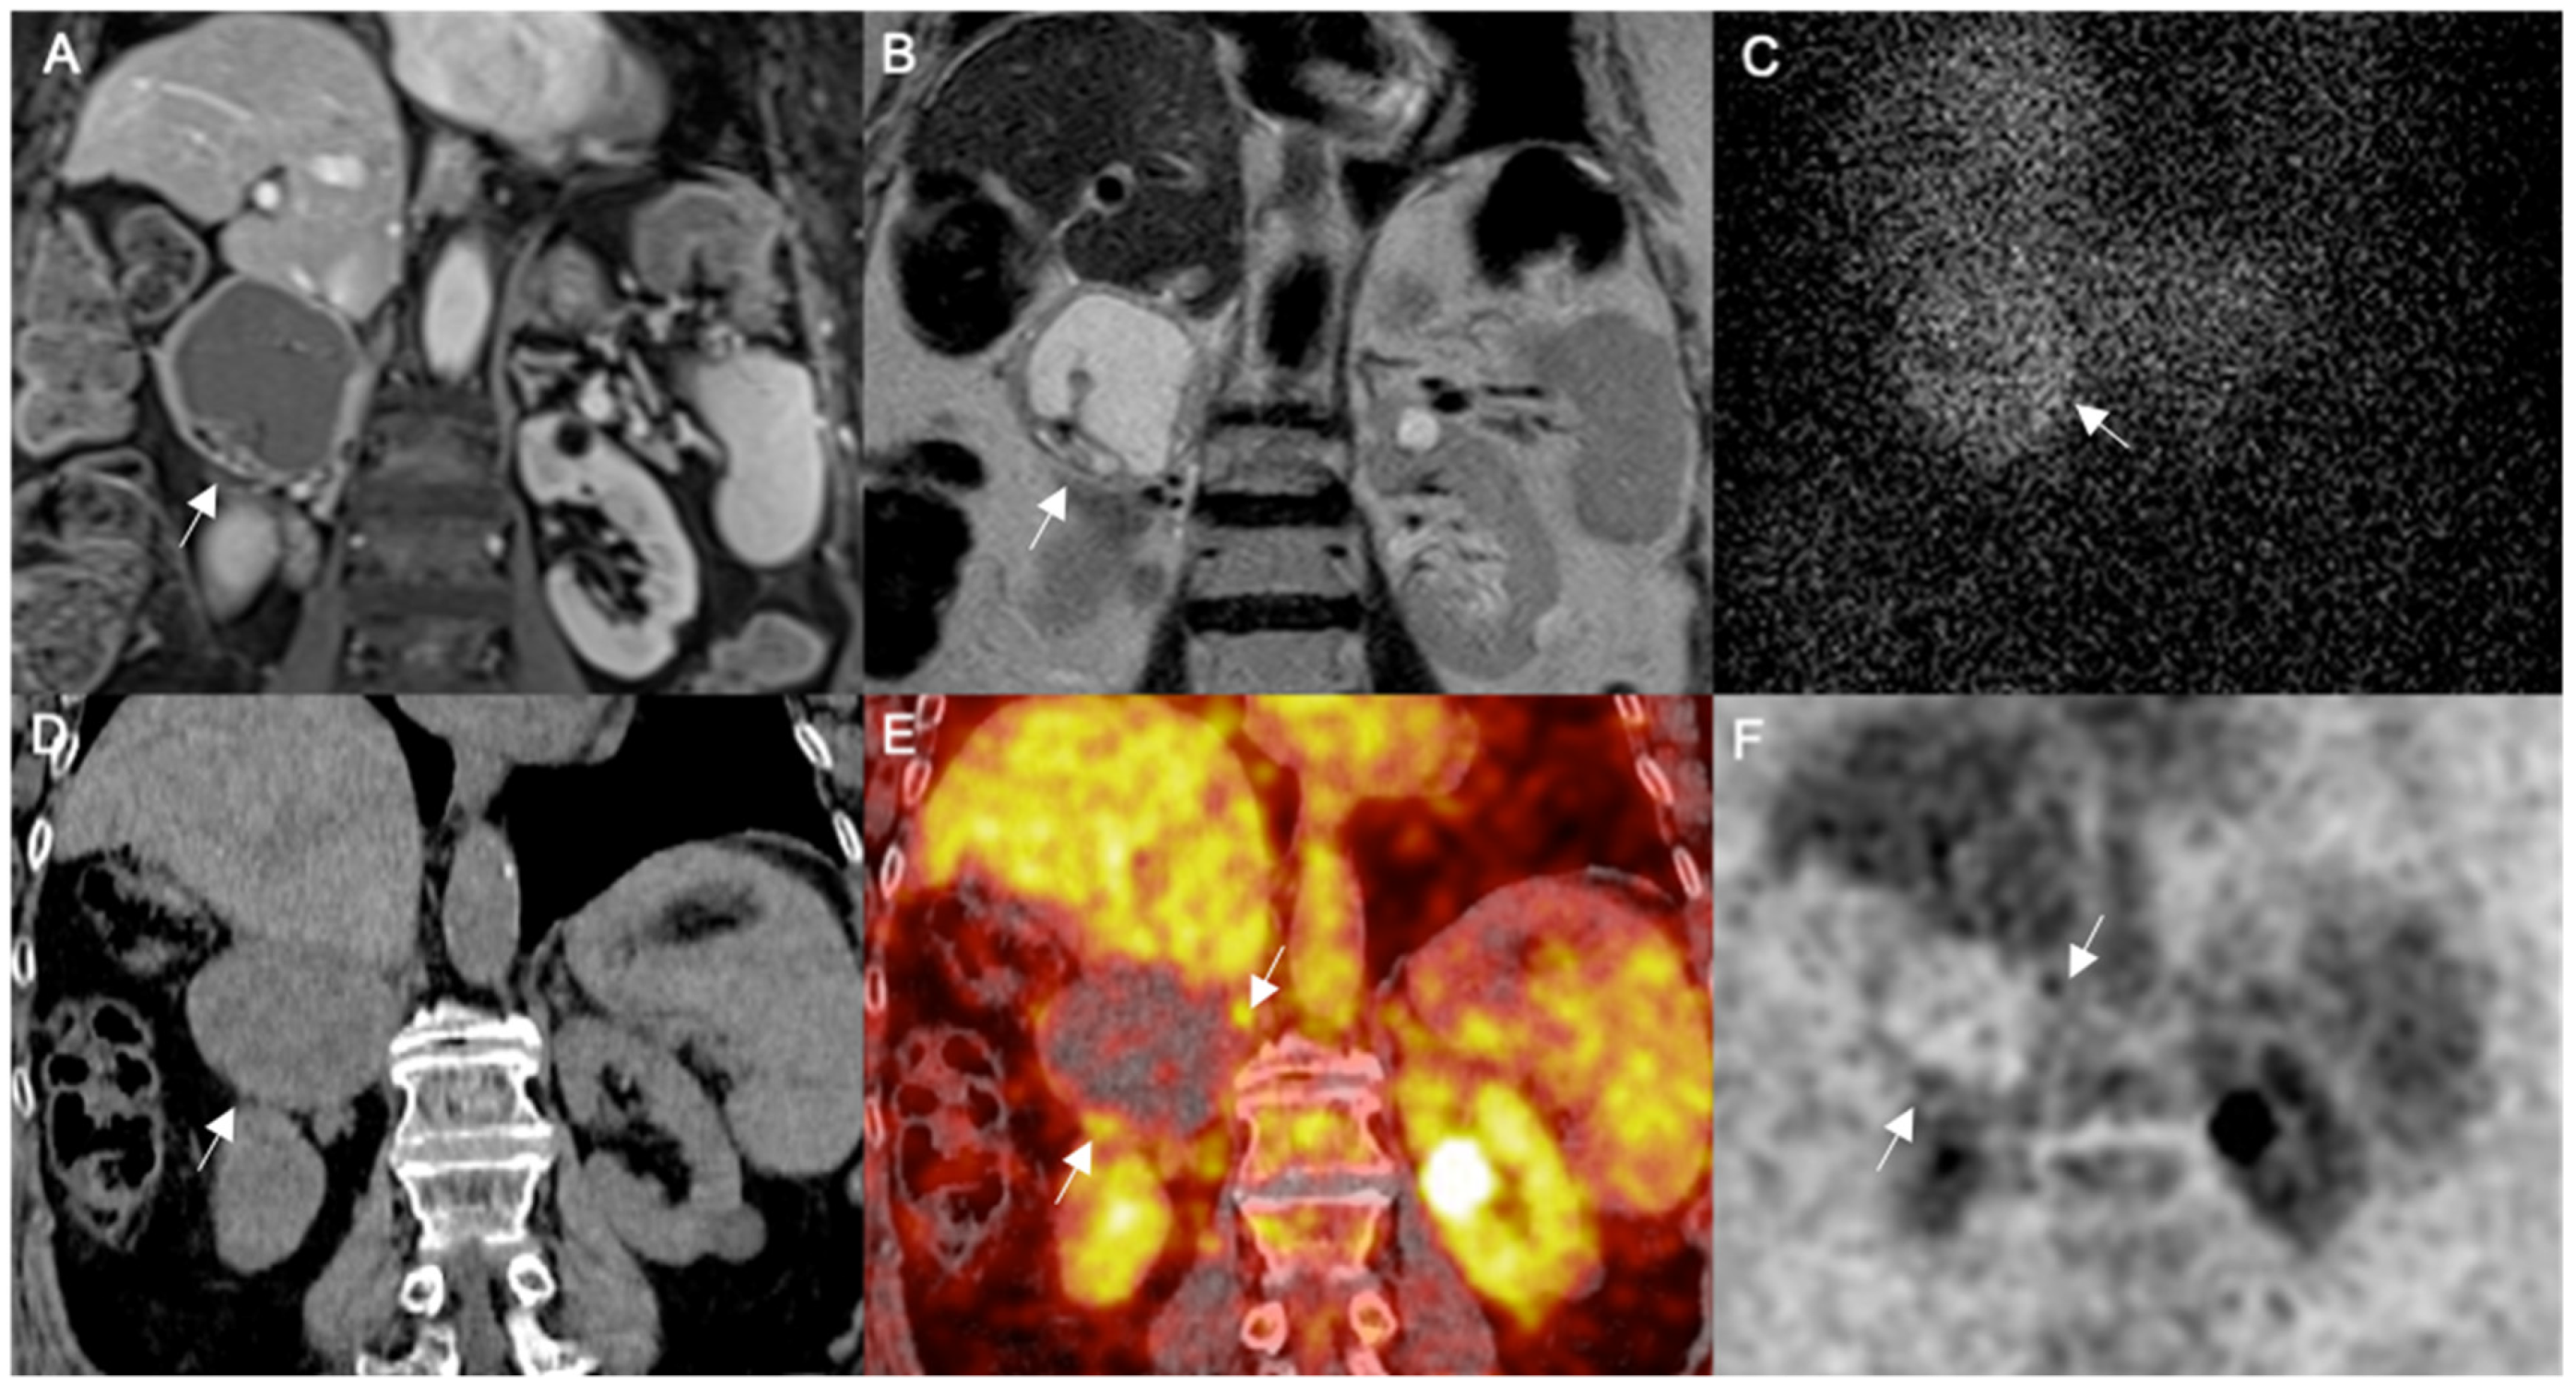

Figure 2. Right adrenal partially cystic pheochromocytoma. MR coronal images represented by T1-WI (A) and T2-WI (B) show a partially cystic adrenal mass measuring 5 cm (arrows). Planar adrenal scintigraphy with 131I MIBG in anterior view at 48 h after tracer injection (C) shows inhomogeneous tracer uptake in the adrenal lesion (arrow). 18FDG PET-MRI coronal image shows a heterogeneously hypointense adrenal mass with regular margins (arrow) on enhanced MRI scan (D); hybrid fused PET-MRI image (E) shows heterogeneous abnormal FDG accumulation in the residual solid component of the adrenal mass (arrows), as also confirmed by the extracted FDG image (F).

In particular, MIBG scans were available in five tumors of which four (80%) showed abnormal heterogeneous residual tracer uptake (one totally cystic, one predominantly cystic, one partially cystic and one hemorrhagic), while the last one (predominantly cystic) was falsely negative. 18F-FDG PET/CT was performed in six lesions showing tracer uptake only by the residual solid component or peripheral rim of tumor structure, of which one was totally cystic, two predominantly cystic, one partially cystic and two hemorrhagic.

18F-FDG PET/MR was performed in two lesions showing tracer uptake only by the residual solid component or peripheral rim of tumor structure, of which one was totally and one was partially cystic. The results of hybrid 18F-FDG imaging showed heterogeneous tracer uptake in the 100% of tumor lesions (n = 8). In these lesions the measurement of SUV max ranged from 1.6 to 10.5. Imaging examples of totally or partially cystic pheos are shown in Figure 1 and Figure 2, respectively.